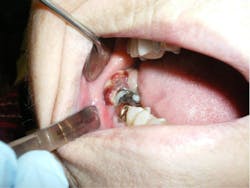

While performing a clinical exam, a 2.5 cm diameter round, greyish-pink mass was observed directly behind tooth no. 31. There was no tenderness to palpation, although the tissue was friable and bled easily. Tooth no. 31 was mobile (class II), with little tenderness to palpation. The other teeth in that quadrant were normal, as was the rest of the intraoral exam. There was no extraoral swelling, no bony expansion with palpation of the mandible, and no cervical lymphadenopathy. The right mandibular division of the trigeminal nerve showed paresthesia upon nerve testing.

In this patient's case, due to the suspicious nature of the lesion being a malignancy, a biopsy was taken at the initial visit. A consultation was also done with the patient’s oncologist, who recommended scheduling a PET CT. Biopsy confirmed metastatic endometrial carcinoma, and the PET CT showed multiple metastatic lesions in the patient’s liver, thoracic aorta, and vertebrae. Most often, prognosis with these lesions is very poor, given that this diagnosis puts patients into a Stage IV situation involving their original cancer.1,2 This held true with our patient; these were not resectable or treatable metastatic lesions.